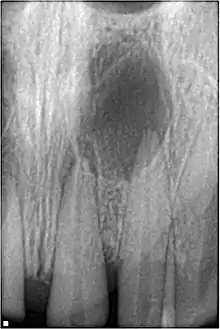

An odontogenic infection is an infection that originates within a tooth or in the closely surrounding tissues.[1] The term is derived from odonto- (Ancient Greek: ὀδούς, odoús – 'tooth') and -genic (Ancient Greek: -γενής, -γενῶς; -genḗs, -genôs – 'birth'). The most common causes for odontogenic infection to be established are dental caries, deep fillings, failed root canal treatments, periodontal disease, and pericoronitis.[2] Odontogenic infection starts as localised infection and may remain localised to the region where it started, or spread into adjacent or distant areas.

It is estimated that 90-95% of all orofacial infections originate from the teeth or their supporting structures and are the most common infections in the oral and maxilofacial region.[3] Odontogenic infections can be severe if not treated and are associated with mortality rate of 10 to 40%.[4] Furthermore, about 70% of odontogenic infections occur as periapical inflammation, i.e. acute periapical periodontitis or a periapical abscess.[3] The next most common form of odontogenic infection is the periodontal abscess.[3]

Sinusitis is inflammation of the paranasal air sinuses. Odontogenic sinusitis is an inflammatory condition of the paranasal sinuses that is the result of dental pathology, most often resulting from prior dentoalveolar procedures, infections of maxillary dentition, or maxillary dental trauma.[5] Infections associated with teeth may be responsible for approximately 20% of cases of maxillary sinusitis.[6] The cause of this situation is usually a periapical or periodontal infection of a maxillary posterior tooth, where the inflammatory exudate has eroded through the bone superiorly to drain into the maxillary sinus. Medical management and treatment of the underlying dental pathology remains a critical initial step in the treatment of odontogenic sinusitis, however recent literature suggests that a significant portion of patients may require endoscopic sinus surgery for successful disease resolution.[5] Once an odontogenic infection involves the maxillary sinus, it is possible that it may then spread to the orbit or to the ethmoid sinus.[6]